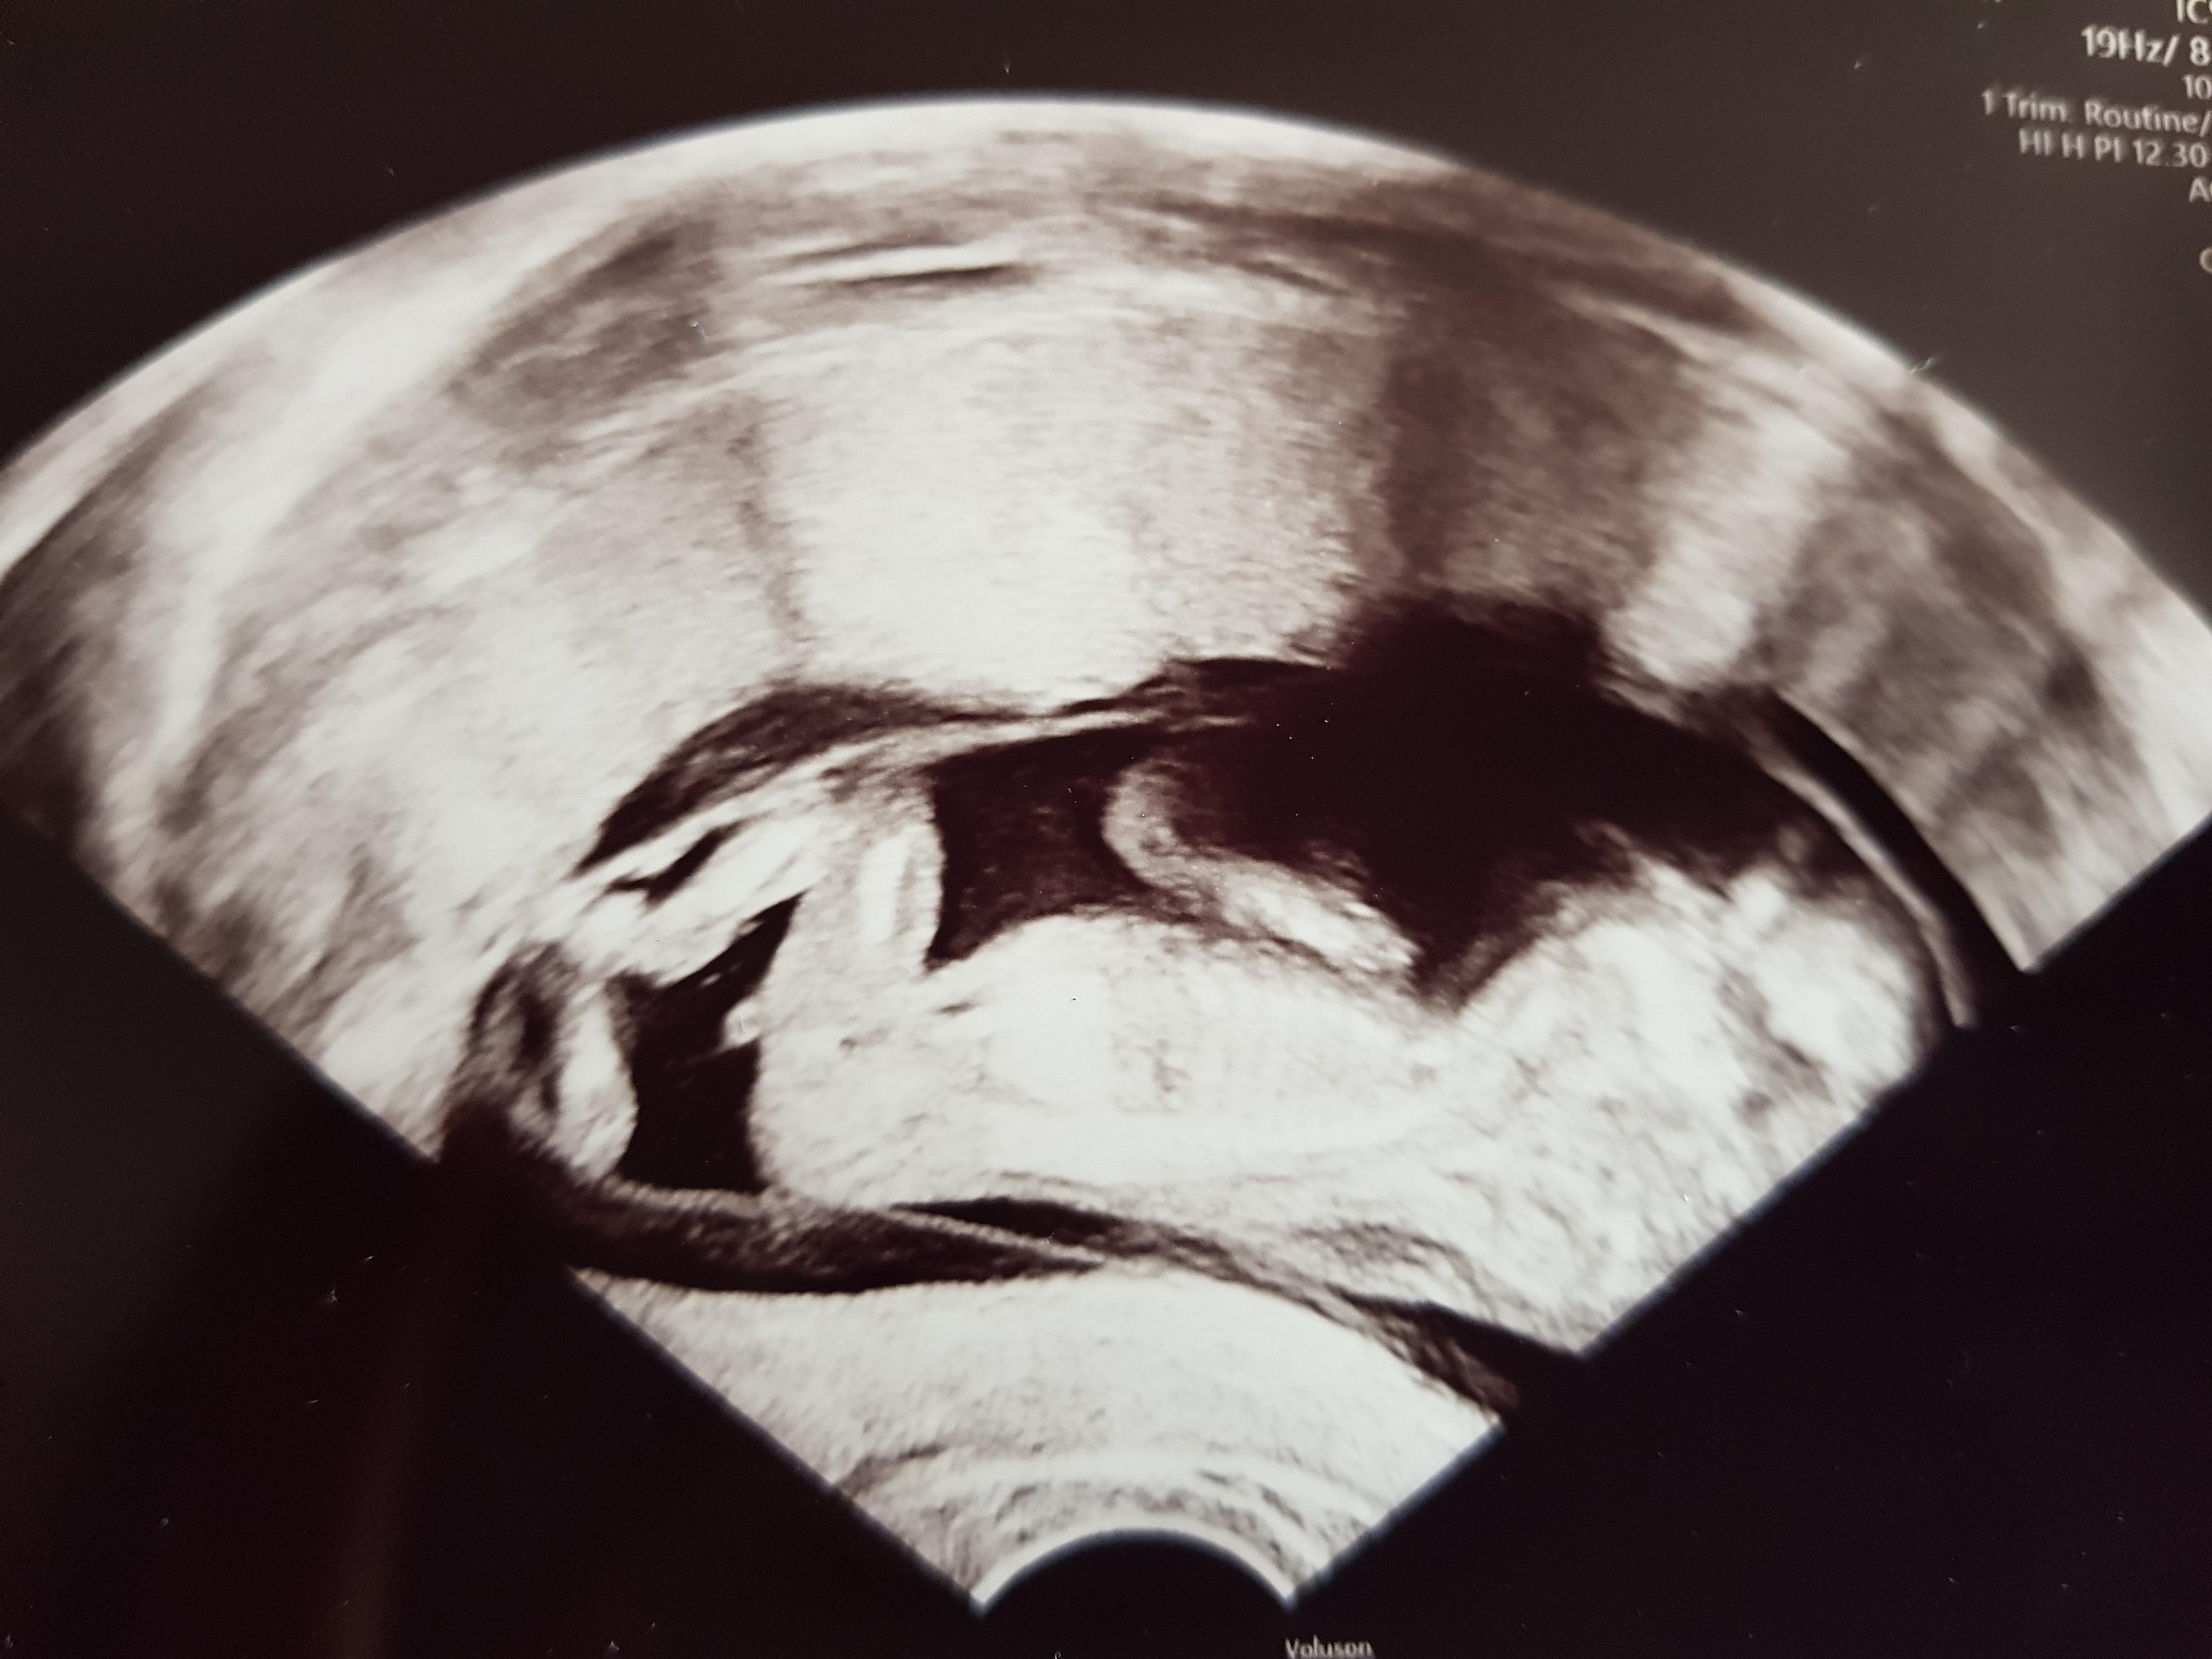

Geschlecht erkennen baby ultraschall. Hallo Ihr Lieben, für alle UltraschallGeschlechtserkennerExperten unter Euch Erkennt man auf dem US schon das Geschlecht des Baby?. Wir wissen das Geschlecht / Schwanger / labellda / vlog Duration 1406. Junge oder Mädchen, Papa beim Ultraschall bei der Geschlechtsbestimmung Viele Eltern möchten gern wissen, obdas Baby ein Mädchen oder Junge ist Doch ab wann kann der Arzt dazu eine Aussage treffen?.

Liegt das Baby beim Ultraschall auf dem Rücken und der Winkel der Noppe zur Wirbelsäule beträgt weniger als 30 Grad, deutet dies auf ein Mädchen hin Ist der Winkel größer als 30 Grad, wird es wohl ein Junge Mit dieser Art der Bestimmung lässt sich das Geschlecht des Babys relativ früh feststellen. 13 SSW Hallo ihr, normal bin ich immer stiller Mitleser, aber diesmal will ich auch mal eure Meinung hören Ich bin aktuell 124 und hab dieses Ultraschallbild heute erhalten Meine Ärztin meint, sie kann noch kein Geschlecht erkennen. Es ist ein Mädchen / so reagiert er / Ultraschall / Labellda Labellda Loading Unsubscribe from Labellda?.

13 SSW Hallo ihr, normal bin ich immer stiller Mitleser, aber diesmal will ich auch mal eure Meinung hören Ich bin aktuell 124 und hab dieses Ultraschallbild heute erhalten Meine Ärztin meint, sie kann noch kein Geschlecht erkennen. Es antwortet Prof Dr B Joachim Hackelöer Chefar. Die Frauenärztin hat bei der Untersuchung zum Geschlecht.

Ganz besonders zu Beginn der Schwangerschaft, wenn es auf dem Ultraschall noch gar nichts zu sehen gibt Das Geschlecht des Babys lässt sich im 4 Monat der Schwangerschaft per Ultraschall bestimmen. Geschlecht erkennen Hallo ihr Lieben!. 13 SSW Hallo ihr, normal bin ich immer stiller Mitleser, aber diesmal will ich auch mal eure Meinung hören Ich bin aktuell 124 und hab dieses Ultraschallbild heute erhalten Meine Ärztin meint, sie kann noch kein Geschlecht erkennen.